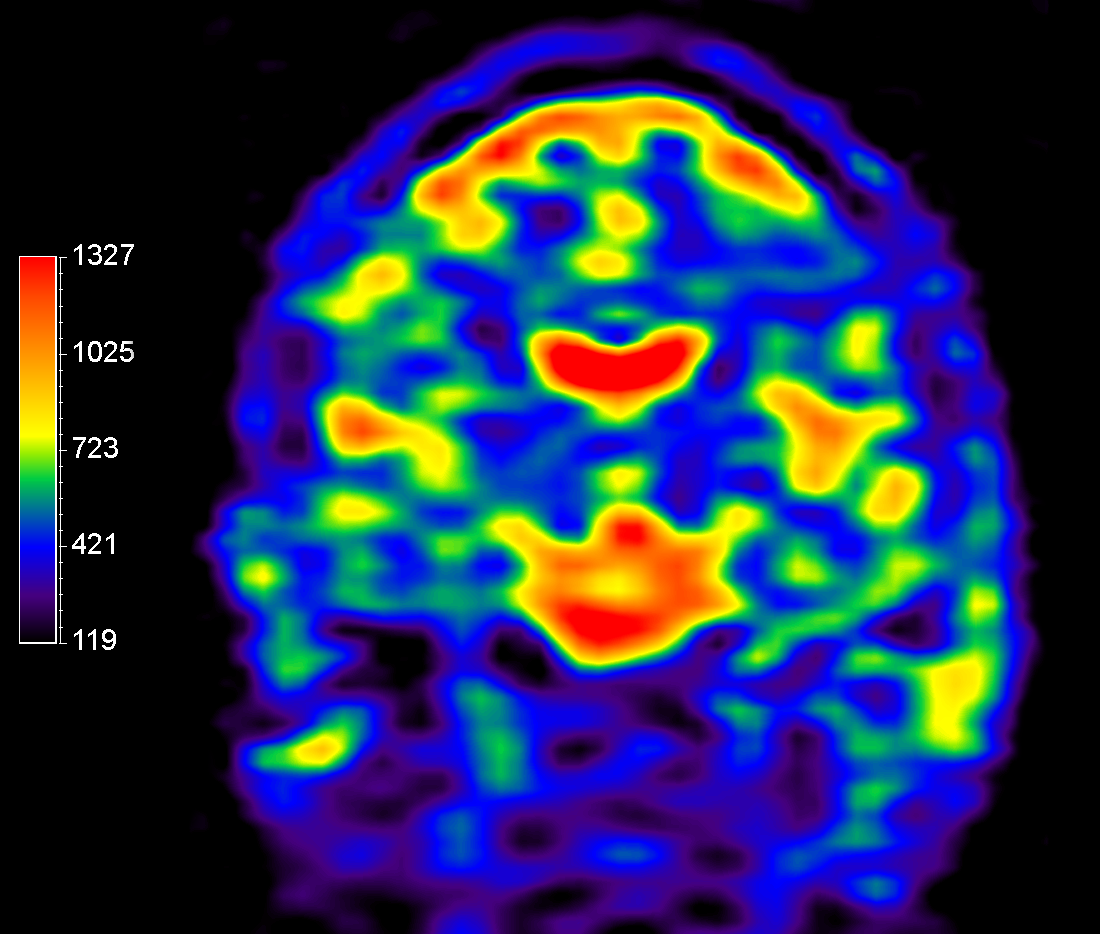

23Na bFFE (axial reformat)